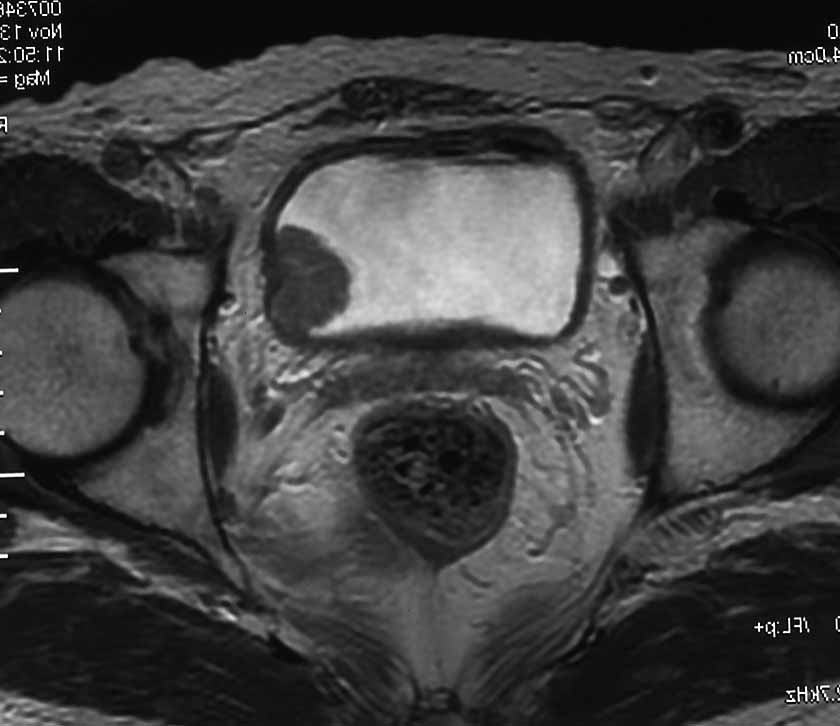

⑤CT、MRI

腫瘍の浸潤度や、リンパ節、遠隔転移の有無につき検査します。